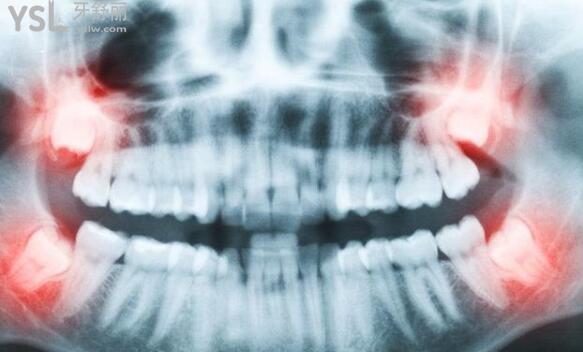

宁波口腔微创舒适拔智齿和普通的有啥区别?

医学已进入微创无疼痛时代,拔牙也不例外,

用**充分证明微创无疼痛拔牙技术以其创伤小,痛苦轻,术后并发症少的优点,

在阻生智齿拔除中具有明显的优势,值得和大家分享并推广,以便让顾客得到较佳的治疗成效。

智齿对于正常的成长来说并不是必须的,对于牙齿提供的拒绝能力智齿作用不大。

在口腔科,想要拔智齿,其实是需要满足一定条件的:

1、蛀牙

如果智齿出现蛀牙,如果补牙存在一定难度,其实不妨一次性拔掉以免除后顾之忧。

2、导致邻牙病变

比如x光诊断,因为智齿的成长很容易影响到第二磨牙的清洁问题,还有可能会诱发一定炎症。

3、引发冠周炎

随着年龄的增长,牙弓会变小,当智齿长出来的时候患者就会出现胀痛以及疼痛的感觉,很容易导致炎症出现。

4、智齿阻生

这种情况不容易处理,这是牙齿埋在齿槽骨里边的一种情况,很容易导致炎症出现,如果存在这种情况一定要及时处理。

5、牙痛明显

如果在长智齿后经常性出现不明原因牙痛,那么也需要医生考虑拔除。